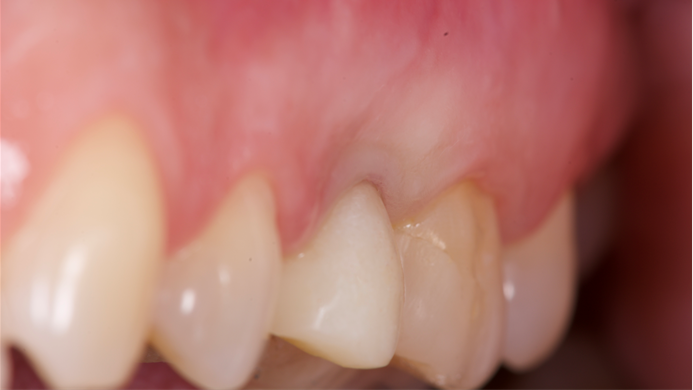

Clinical case: Full-arch implant treatment with immediate loading & extraction implantation

- Courtesy of Dr. Laurent Sers, France -

AnyRidge, R2GATE, guided surgery, Dr. Laurent Sers, immediate loading, maxilla

Products:

AnyRidge implant system, R2GATE, Digital prosthesis